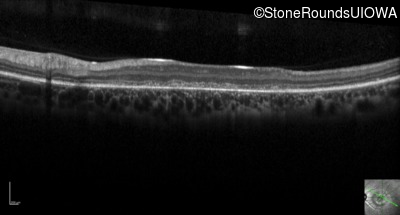

Optical Coherence Tomography - Left - 20/200 -2

Exemplar / OCT Stack